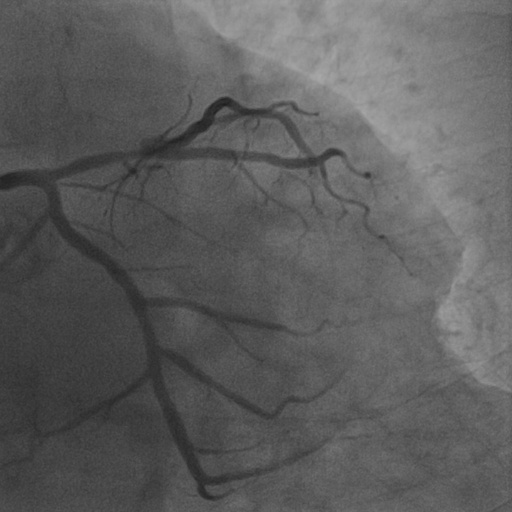

4.1 XACV Dataset

We collect 111 complete records of coronary artery X-ray videos, encompassing the injection, flow through the blood vessels around the heart, and dissipation of the contrast agent. Subsequently, we establish the XACV (X-ray Angiography Coronary Video) dataset. Each video consists of varying numbers of high-resolution coronary artery X-ray images. We invite experienced radiologists to annotate the vascular regions, focusing on one or two frames where the contrast agent is most prominent in each video. The XCAD dataset contains only a single image, and the CADICA video dataset does not provide corresponding ground truth. Therefore, in the following experiments, we conduct all the analyses on our collected XACV dataset and the corresponding GT for each sequence. In Figure 5, we show that compared to other publicly available datasets, XCAD [33] and CADICA [19], our dataset exhibits finer annotations in the vascular regions, providing an advantage for future related tasks. The development and use of our dataset have been approved by our institution’s IRB.